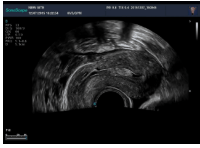

5腔內(nèi)探頭

腔內(nèi)探頭,具有頻率高,圖像分辨率高等特點,不需充盈膀胱,探頭緊貼受檢部位,使盆腔器官處于聲束的近場區(qū)域,圖像更清晰。